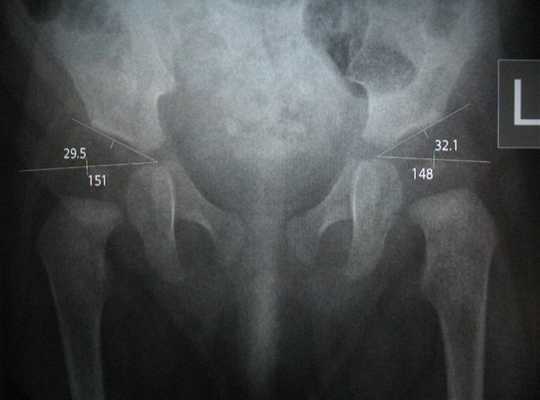

Учитывая угол Идельберга-Франка, угол Виберга и MZ-расстоянини децентрализации, статистическими методами можно выделить нормальные и патологические суставы: у взрослых значения тазобедренного сустава от 6 до 15 указывают на нормальную форму сустава; значения между 16 и 21 указывают на небольшую деформацию, а значения от 22 и выше указывают на серьезную деформацию, у детей значения от 15 и выше являются патологическими.

На рентгене признаки вывиха или дисплазии тазобедренных суставов визуализируются в виде вертикального и бокового смещений головки бедренной кости от вертлужной впадины тазовой кости (измеряемого на полученном снимке и сопоставляемого с анатомической нормой). Поверхность головки бедра часто не соответствует вертлужной впадине тазовой кости, например, при большом размере головки и недостаточной глубине впадины. А угол наклона плоскости входа в нее превышает норму.

Также отмечаются смещение центра вертлужной впадины, уменьшение или увеличение шеечно-диафизарного угла (определяемого между вертикальными осями шейки бедренной кости и ее телом — диафизом).

Следует иметь в виду, что рентген костей таза и тазобедренных суставов у детей раннего возраста не показывает точных очертаний суставных структур, так как их основная ткань - хрящевая, которую рентгеновские лучи не отображают. Поэтому интерпретацию полученной рентгенограммы - с определением смещения головки бедренной кости по отношению к вертлужной впадине тазовой кости - проводят с помощью накладывания на снимок специальной сетки, основные и вспомогательные линии которой соответствуют анатомически нормальному расположению структур сустава. Используя данные линии, измеряются различные параметры, в том числе центр вертлужной впадины и степень наклона ее крыши (ацетабулярный угол), угол отклонение шейки бедра вперед и т.д.